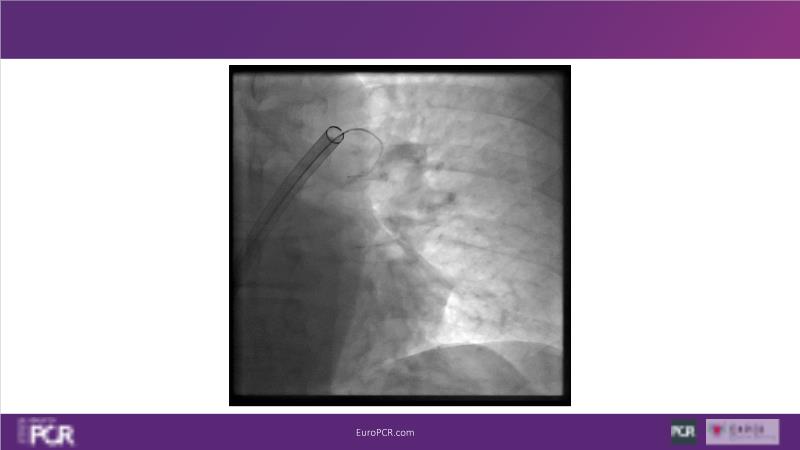

Why mechanical thrombectomy should be considered in the management of acute pulmonary embolism

In this EuroPCR 2024 session, study the case of a patient with high-risk pulmonary embolism and another with intermediate to high-risk pulmonary embolism, delve into discussions on clinical evidence for mechanical thrombectomy in pulmonary embolism, acquire skills to evaluate eligibility for mechanical thrombectomy, and learn how to integrate such technique in local pulmonary embolism patient pathway.